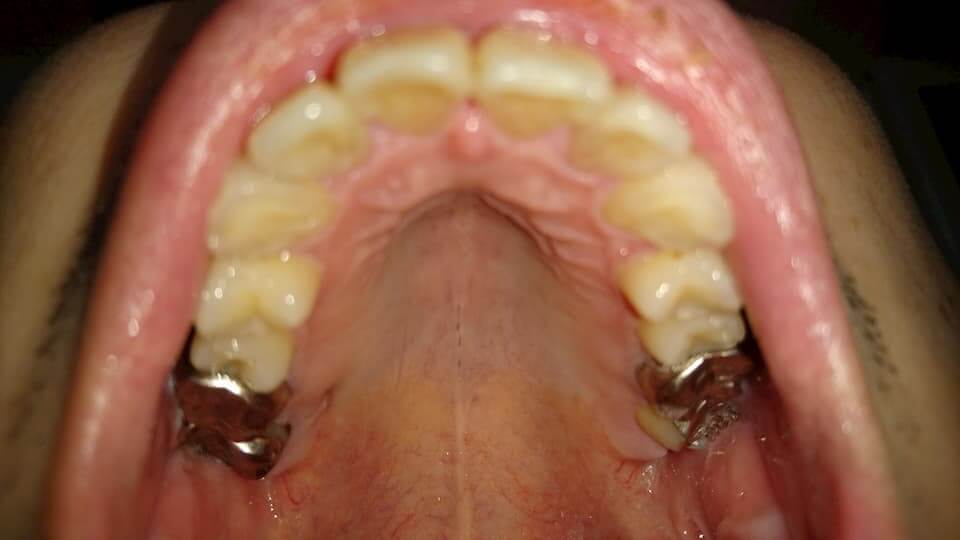

歯の写真